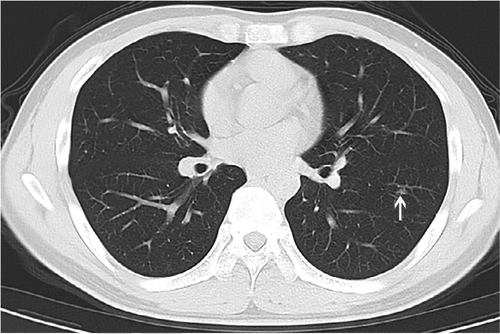

Now, maybe that image was unrepresentative or included by error, but they show this one as well, with a handy arrow:

According to this paper, tiny random opacities are now diagnostic of Covid-19.

I’m getting snarky here, this is only 2 images out of the dozen or so in the paper, but would anyone like to guess what percentage of healthy patients have a tiny vague opacity or scattered basal interstitial markings?